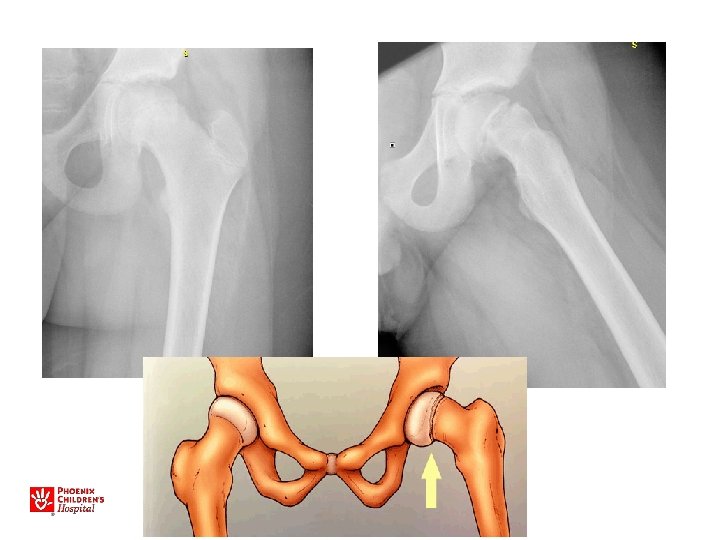

Unstable SCFE • • • (5% of slips) Unable to bear weight or mobilize “Hip fracture” May have antecedent pain Minimal trauma High rate of osteonecrosis (20 -50%)

11 yo M, acute unstable SCFE

Avascular Necrosis of the Hip

Acute, Unstable SCFE • Capsulotomy to decompress – Either anterior open approach – Capsular decompression • Open reduction – Surgical hip dislocation